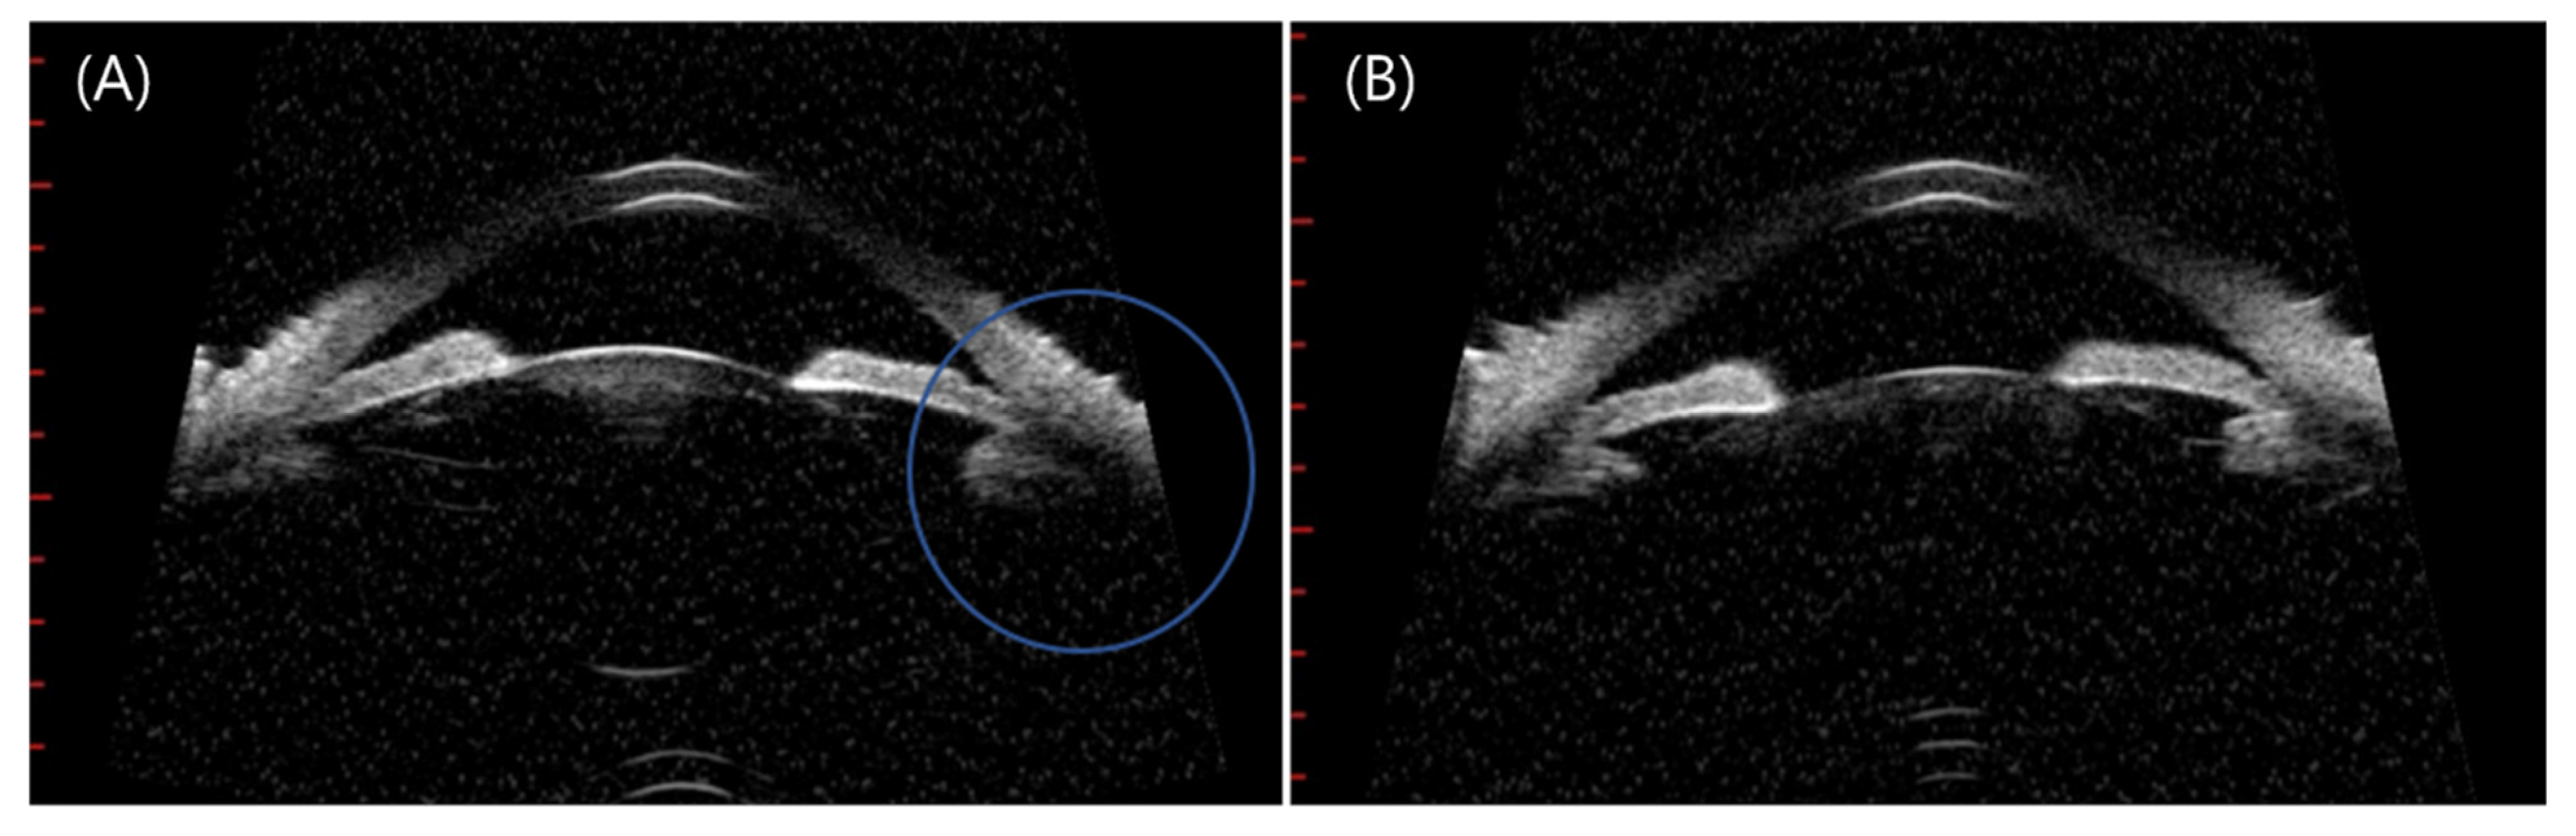

Further, we hypothesized the main etiology of the four angle-closure attack cases following COVID-19 vaccination is ciliary body swelling due to uveitis. Not all patients were photographed, and Ultrasound biomicroscopy figures were available in one case in our study. Figure 4 shows swelling of the ciliary body six days after vaccination that led to zonule laxity accompanied by phacodonesis, causing a closed-angle attack. The swollen ciliary body may lead to anterior shifting of the lens and, consequently, to a myopic shift. Although we only compared SE before and after the ACG attack in case #16, the other cases were more likely to have myopic SE in the affected eyes than the fellow eye. The median age of our four ACG patients was 69.5 years, and the women to men ratio was 3:1, similar to that in a multi-centered Korean study with an average age of 64.28 years and sex ratio of 3.13:1 [26]. Axial lengths of our ACG subjects were 21.84 mm, 22.95 mm, 22.37 mm, and 23.71 mm, which were similar with average 22.42 mm in one of acute primary angle-closure studies in Korea [27]. Conversely, our subjects’ anterior chamber depths (ACDs) were 2.19 mm, 2.19 mm, 2.89 mm, and 2.31 mm, which were deeper than the average ACDs in ACG cases in Korea (1.87 mm) in 2017 [27].

Figure 4.

(Patient 17) (A) Right eye of a 64-year-old man, who had no previously diagnosed disease. He visited our clinic complaining of pain and redness in the right eye 6 days after AZD1222 inoculation. (B) His left eye shows a normal peripheral angle and no zonule laxity. His initial IOP was 34 mmHg associated with shallowing of the anterior chamber peripherally in the right eye. His bio-microscopy images show anterior bowing of the peripheral iris and ciliary swelling in the right eye than the left eye, which caused phacodonesis of the right eye and closure of the iridocorneal angle in the right eye. An acute attack of angle closure was diagnosed, treatment with laser peripheral iridotomy was attempted, and his IOP dropped to 10 mmHg.